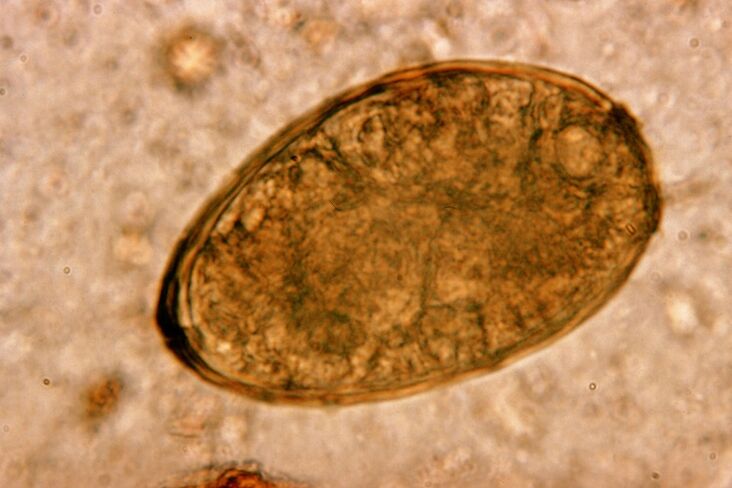

Метилът живее в белите дробове по двойки, образувайки кисти в бронхите. Заразяването става при ядене на раци и раци, заразени с паразита. Попаднал в стомашно-чревния тракт, белодробният метил прониква през перитонеума и през диафрагмата достига белите дробове, причинявайки упорита кашлица у пациента.

Малкият хелминт белодробен метил, принадлежащ към класа на трематодите, е "специализиран" в паразитирането специално в белите дробове. Той причинява много по-сериозни проблеми в дихателната система от аскаридите например.

На мястото на локализирането му се появяват инфилтрати и се развиват кръвоизливи, в резултат на което се появяват кухини, пълни с разлагащи се метаболити на червеи, мъртви паразити и белодробна тъкан. Вредата от белодробния метил се утежнява още повече от факта, че той е дълготраен и може да живее в тялото на гостоприемника до 20 години.